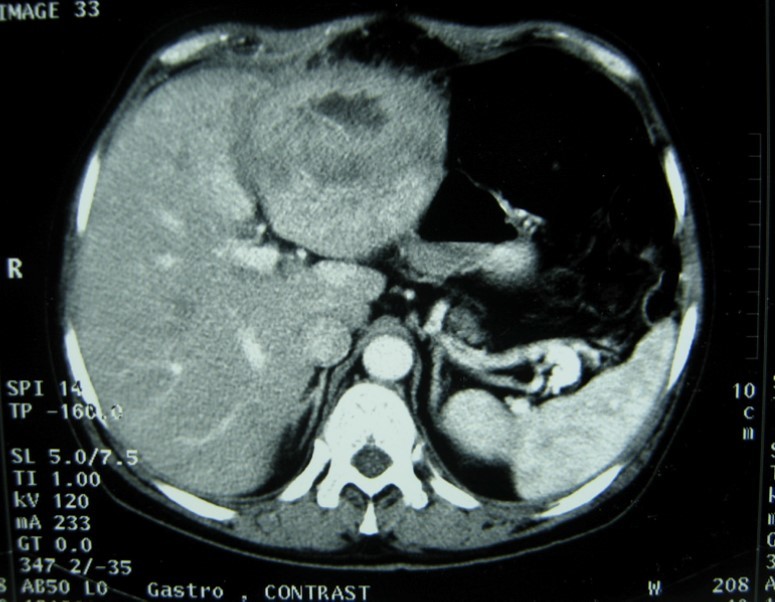

A 17-year-old young man admitted to our department with the complaint of abdominal pain localized in the left upper quadrant for the last 3 months. His physical examination revealed a splenomegaly. Immunoblot assay for Echinococcus was positive. His laboratory tests showed normal results of the serum and urine examinations, No eosinophilia was found. Chest X-ray revealed no pathological signs. An abdominal ultrasonography showed a 20 cm multivesicular cystic mass of spleen (figure 1). Contrast enhanced CT scans detected a huge single 20×16×18cm cystic mass located in the spleen. It had well-defined borders and contained multiple, round, daughter cysts in the periphery of the lesion with calcification (Figure 2, Figure 3, Figure 4). The patient underwent a laparotomy. A large splenic cystic mass was identified, attached to diaphragm, and tail of the pancreas (figure 5). The abdomen was packed with 10% hypertonic saline soaked pads in order to protect peritoneal soilage. A partial cystectomy without splenectomy was performed. Histologic examination of the specimen resection showed an echinococcal organism residing within the hydatid cyst . The patient was discharged after 4 postoperative days. 600 mg per a day of Albendazole therapy was instaured postoperatively and continued for 6 months. Two years after surgery the patient is well with disease free.

Figure 3.CT showing a huge single 20×16×18cm cystic mass located in the spleen

Ct scan is useful for diagnosis and screening, although there are a variety of pathognomonic signs of hydatid disease on imaging, they are not always present. Other cystic lesions of spleen, such as abscess, hematoma, or pseudocyst may be a diagnostic dilemma 5, 12. CT may show the cystic lesion with or without daughter cysts within the spleen with an attenuation value near that of water without any contrast enhancement 10, 11. Hematological examination may reveal eosinophilia. Immunoelectrophoresis, enzyme-linked immunosorbent assay (ELISA), latex agglutination, and indirect haemagglutination test are helpful for the diagnosis 13. A negative serology does not rule out cystic echinococcosis . In these cases the diagnosis can be difficult . Although the sensitivity of serological testing is not clearly dependent on the extent of disease, it does appear to be dependent on cyst stage. 14. echinococcal IgG ELISA test has perhaps the highest positive predictive value among the available serological tests, but unfortunately may only have a negative predictive value of <90% 14. A rapid immunochromatography test kit using the recombinant Em18 antigen was recently developed. It seems be simple, reliable, and easy-to-use 15.